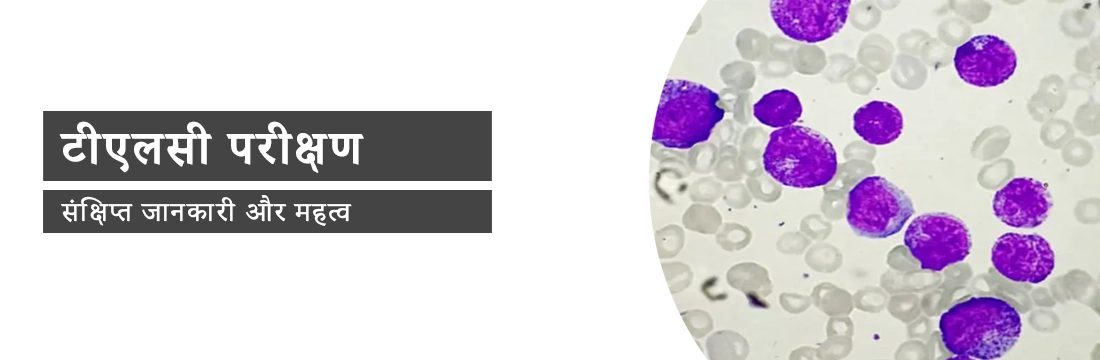

टीएलसी टेस्ट (TLC Test) का मतलब टोटल ल्यूकोसाइट्स काउंट (Total Leucocyte Count) है और सफेद रक्त कोशिकाओं (White Blood Cells) को ल्यूकोसाइट्स (Leukocytes) कहा जाता है। वे हमारी प्रतिरक्षा प्रणाली (Immune System) का महत्वपूर्ण हिस्सा हैं। ये आपके शरीर को बीमारी (Disease) या संक्रमण (Infection) से लड़ने में मदद करते हैं। आपके शरीर में संक्रमण का संकेत टीएलसी (Increased TLC Count) में वृद्धि है।

टीएलसी परीक्षण केवल एक रक्त परीक्षण (Blood Test) है। इस परीक्षण का उपयोग करके हम आपके रक्त में ल्यूकोसाइट्स-Leukocytes (श्वेत रक्त कोशिकाओं-White Blood Cells) की संख्या की गणना कर सकते हैं। इस अध्ययन को WBC गणना (WBC Count) के रूप में भी जाना जाता है। श्वेत रक्त कोशिकाएं (White Blood Cells) हमारे शरीर की प्रतिरक्षा कोशिकाएं (Immune Cells) हैं जो विभिन्न प्रकार के वायरस (Viruses), बैक्टीरिया (Bacteria) और कीटाणुओं (Germs) से लड़ने में मदद करती हैं। यह किसी भी संक्रमण (Infection), सूजन (Swelling) आदि को ठीक करने में भी मदद करता है।

ये पांचों मिलकर ल्यूकोसाइट्स (Leukocytes) या श्वेत रक्त कोशिकाएं (White Blood Cells) बनाते हैं।